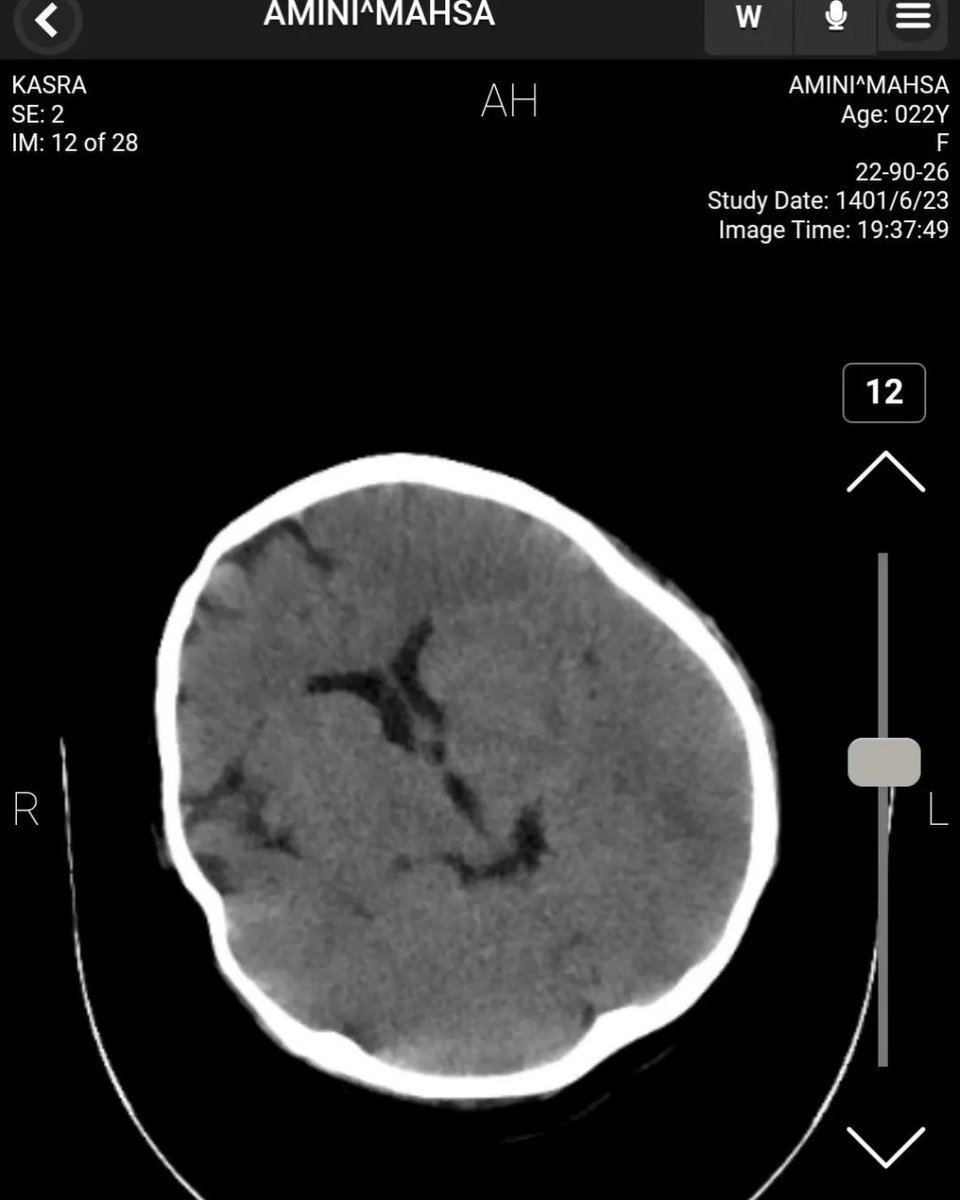

دکتر طاهریان، رزیدنت سال آخر رادیولوژی :

سلام. امروز موفق شدم به سی تی اسکن های مهسا امینی دسترسی پیدا کنم و به عنوان یک رزیدنت سال اخر رادیولوژی و پس از مشورت با یکی از اساتید و یکی از همکاران نوروسرجن ریپورت این سی تی اسکن رو خدمت شما میگم.

تصاویر بطورکامل درویندوهای مختلف ازطریق پکس بیمارستان کسری توسط بنده واستادوهمکار نوروسرجن بررسی شده.پیش ازهرچیزبگویم که پستم برای روشن شدن حقیقت درموردایشان هست وجنبه پزشکی ونه سیاسی دارد

پست من دردفاع ازشواهدیست که درسی تی اسکن ایشان دیده میشود نه دفاع یاحمله به کسی یاحکومتی Image